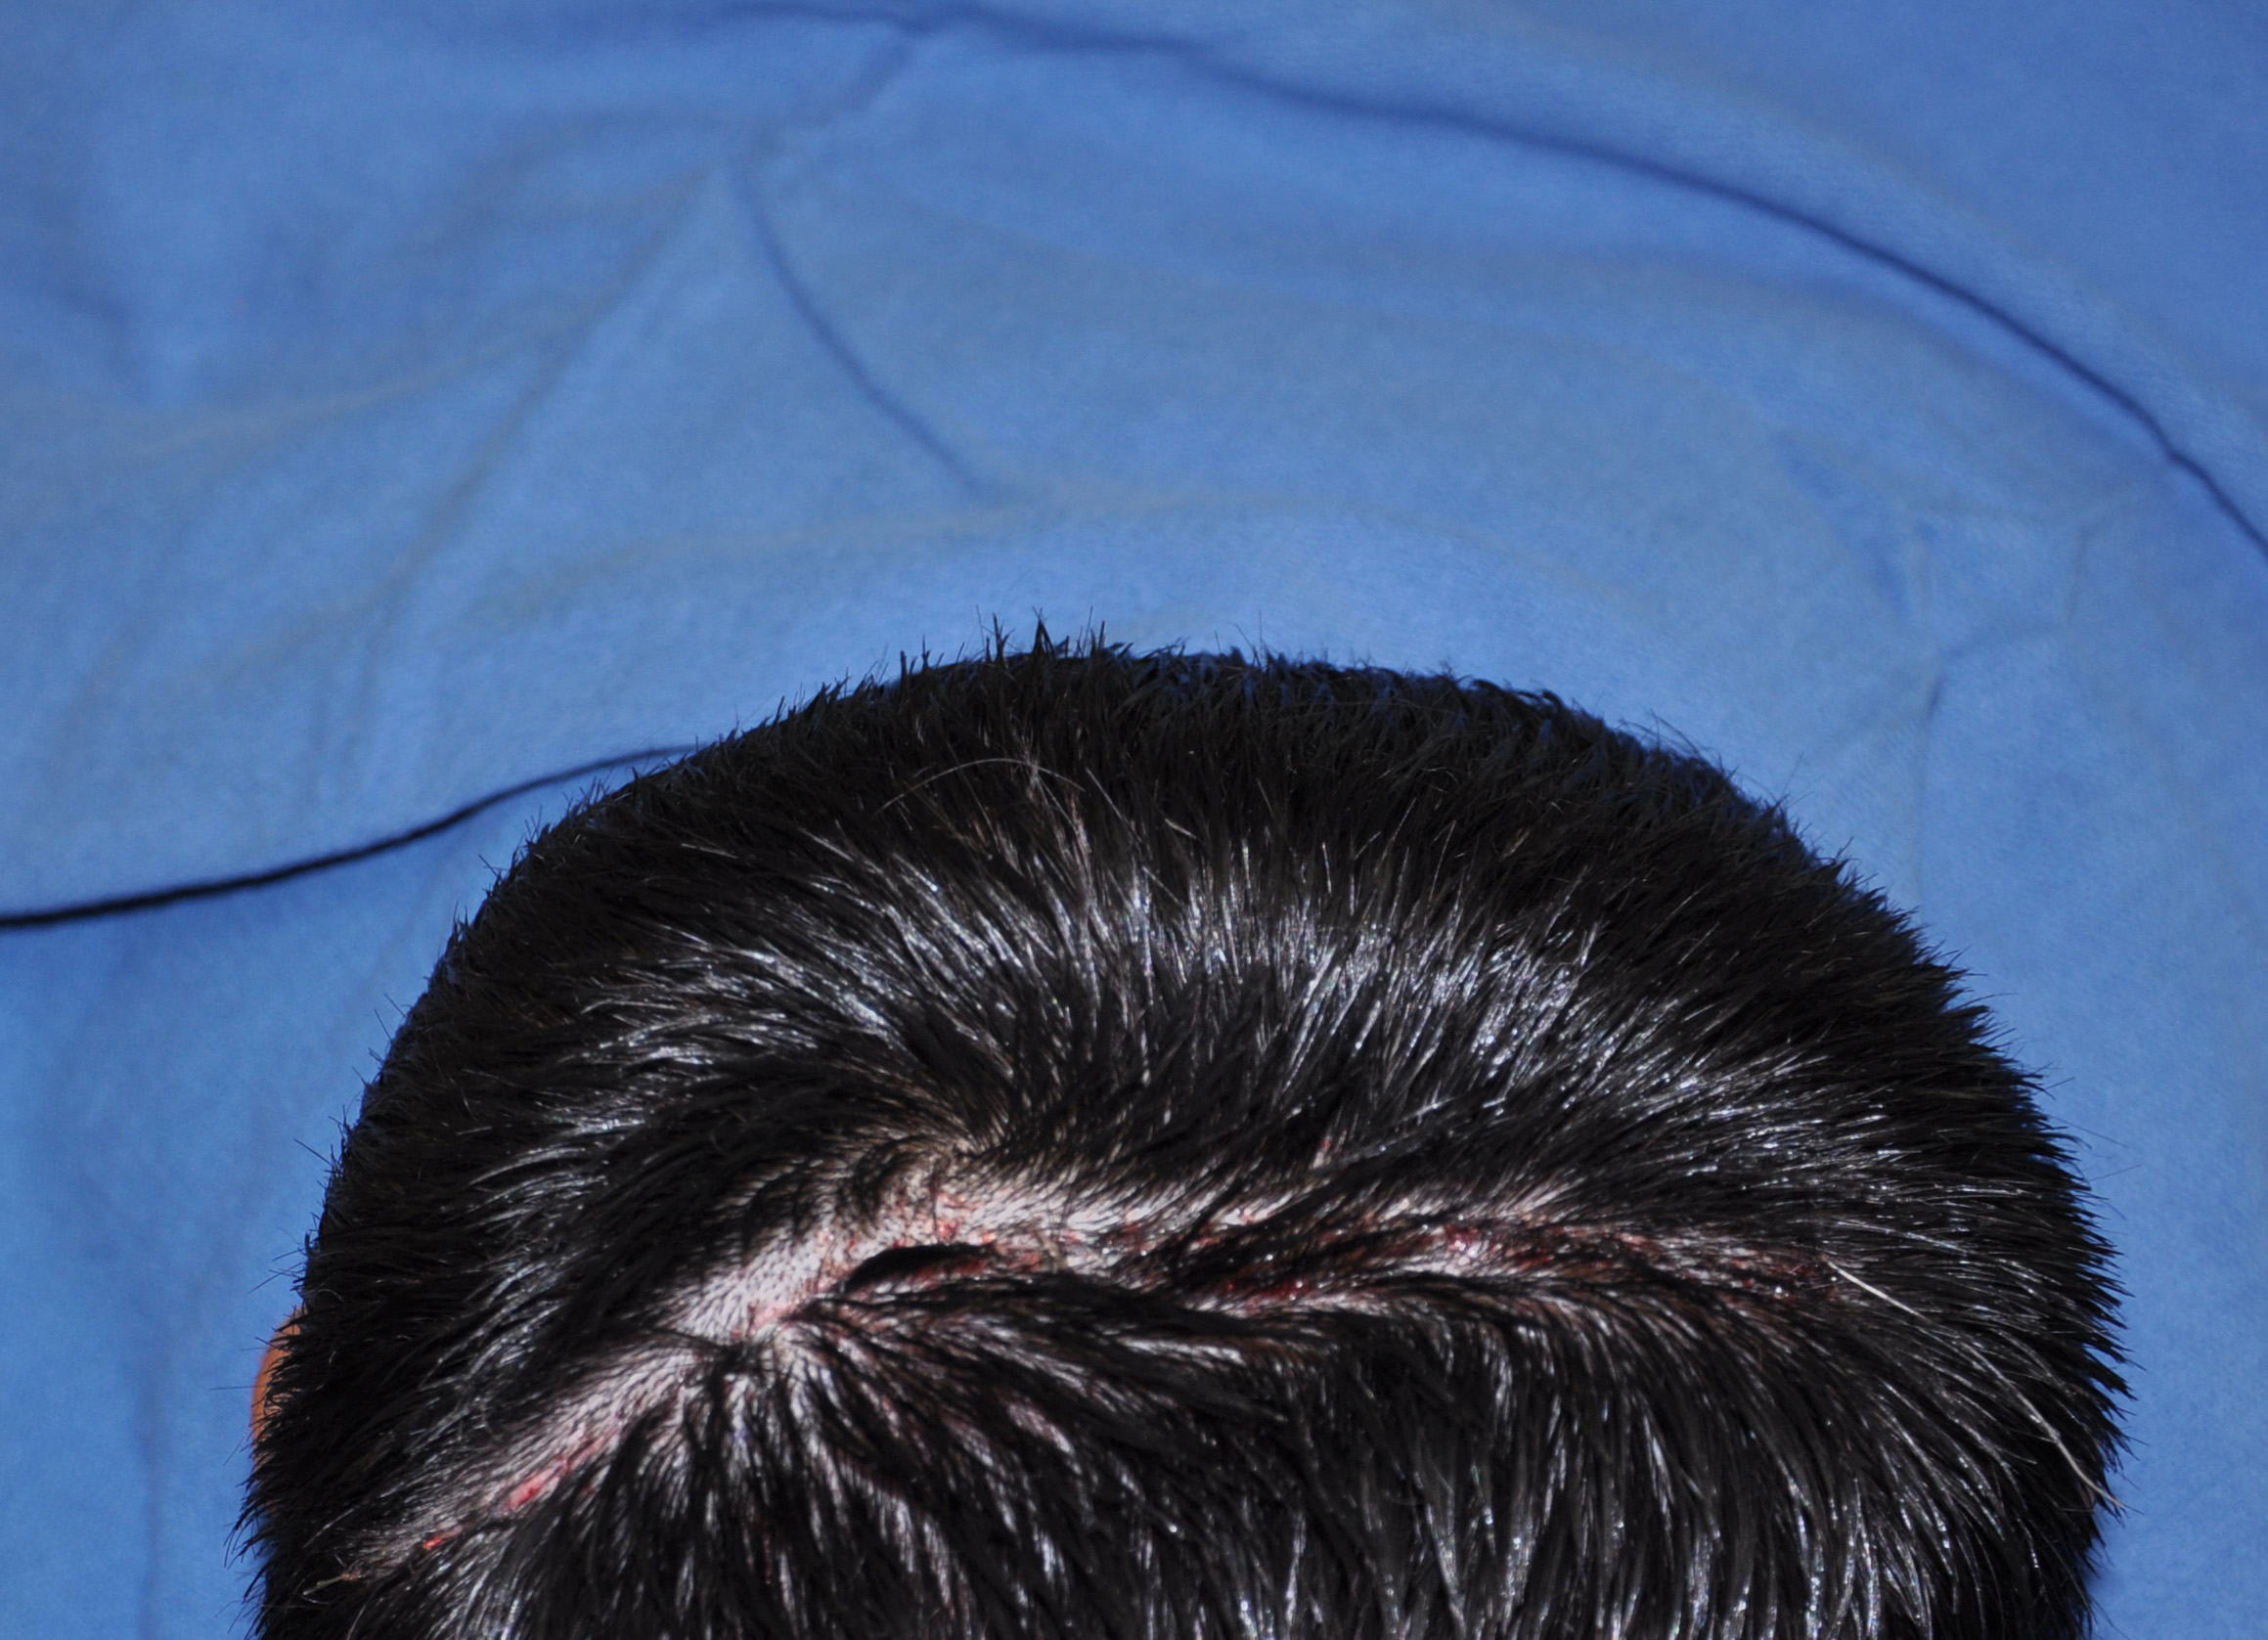

57

Scalp avulsion due to traumatic injury which left a large patch of non-hair bearing scalp.

Hair bearing scalp reconstruction using a first stage tissue expanders and second stage scalp scar removal.